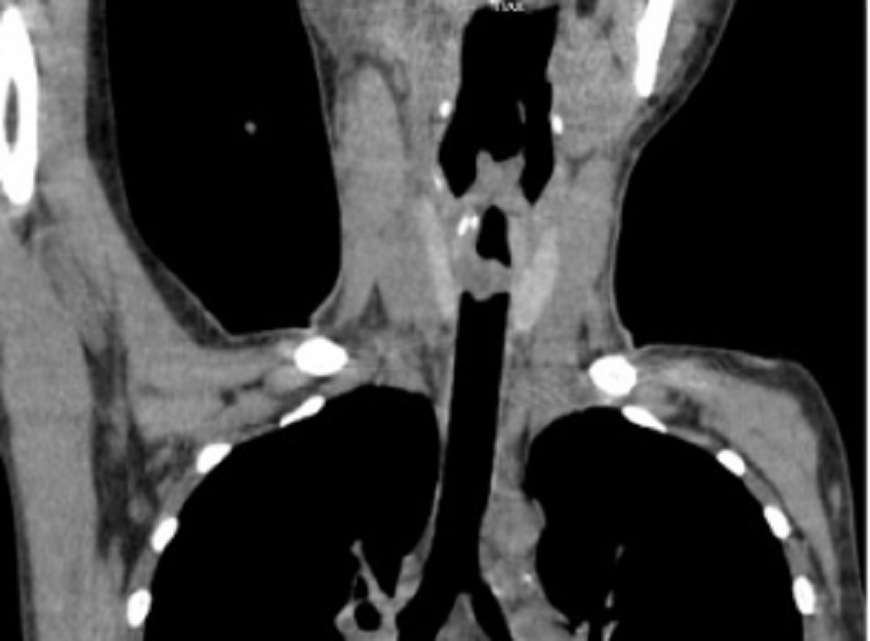

| Khối u lớn gây tắc gần như hoàn toàn khí quản khiến bệnh nhân suy hấp cấp, nguy kịch |

Kết quả chụp cắt lớp vi tính tại Bệnh viện Quân y 175 phát hiện một khối u lớn, kích thước 3x2cm, nằm ở vị trí dưới dây thanh âm. Khối u có nhiều mạch máu trên bề mặt, gây tắc nghẽn gần như hoàn toàn khí quản của người bệnh. Các bác sĩ đã nhanh chóng mở nội khí quản phía dưới đoạn bị khối u gây tắc và cho bệnh nhân thở máy.